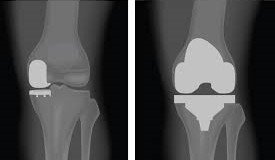

عملية تغيير مفصل الركبة هي إجراء جراحي يتم فيه استبدال الأجزاء التالفة من مفصل الركبة بمكونات صناعية مصممة بدقة لتحاكي حركة المفصل الطبيعي. وذلك قد يكون استبدالاً كاملاً للمفصل، أو استبدالاً جزئيًا بتغيير الأجزاء المتضررة من المفصل بشكل جزئي في بعض الحالات، وذلك حسب حالة المريض. ويُنصح بها في حالات: